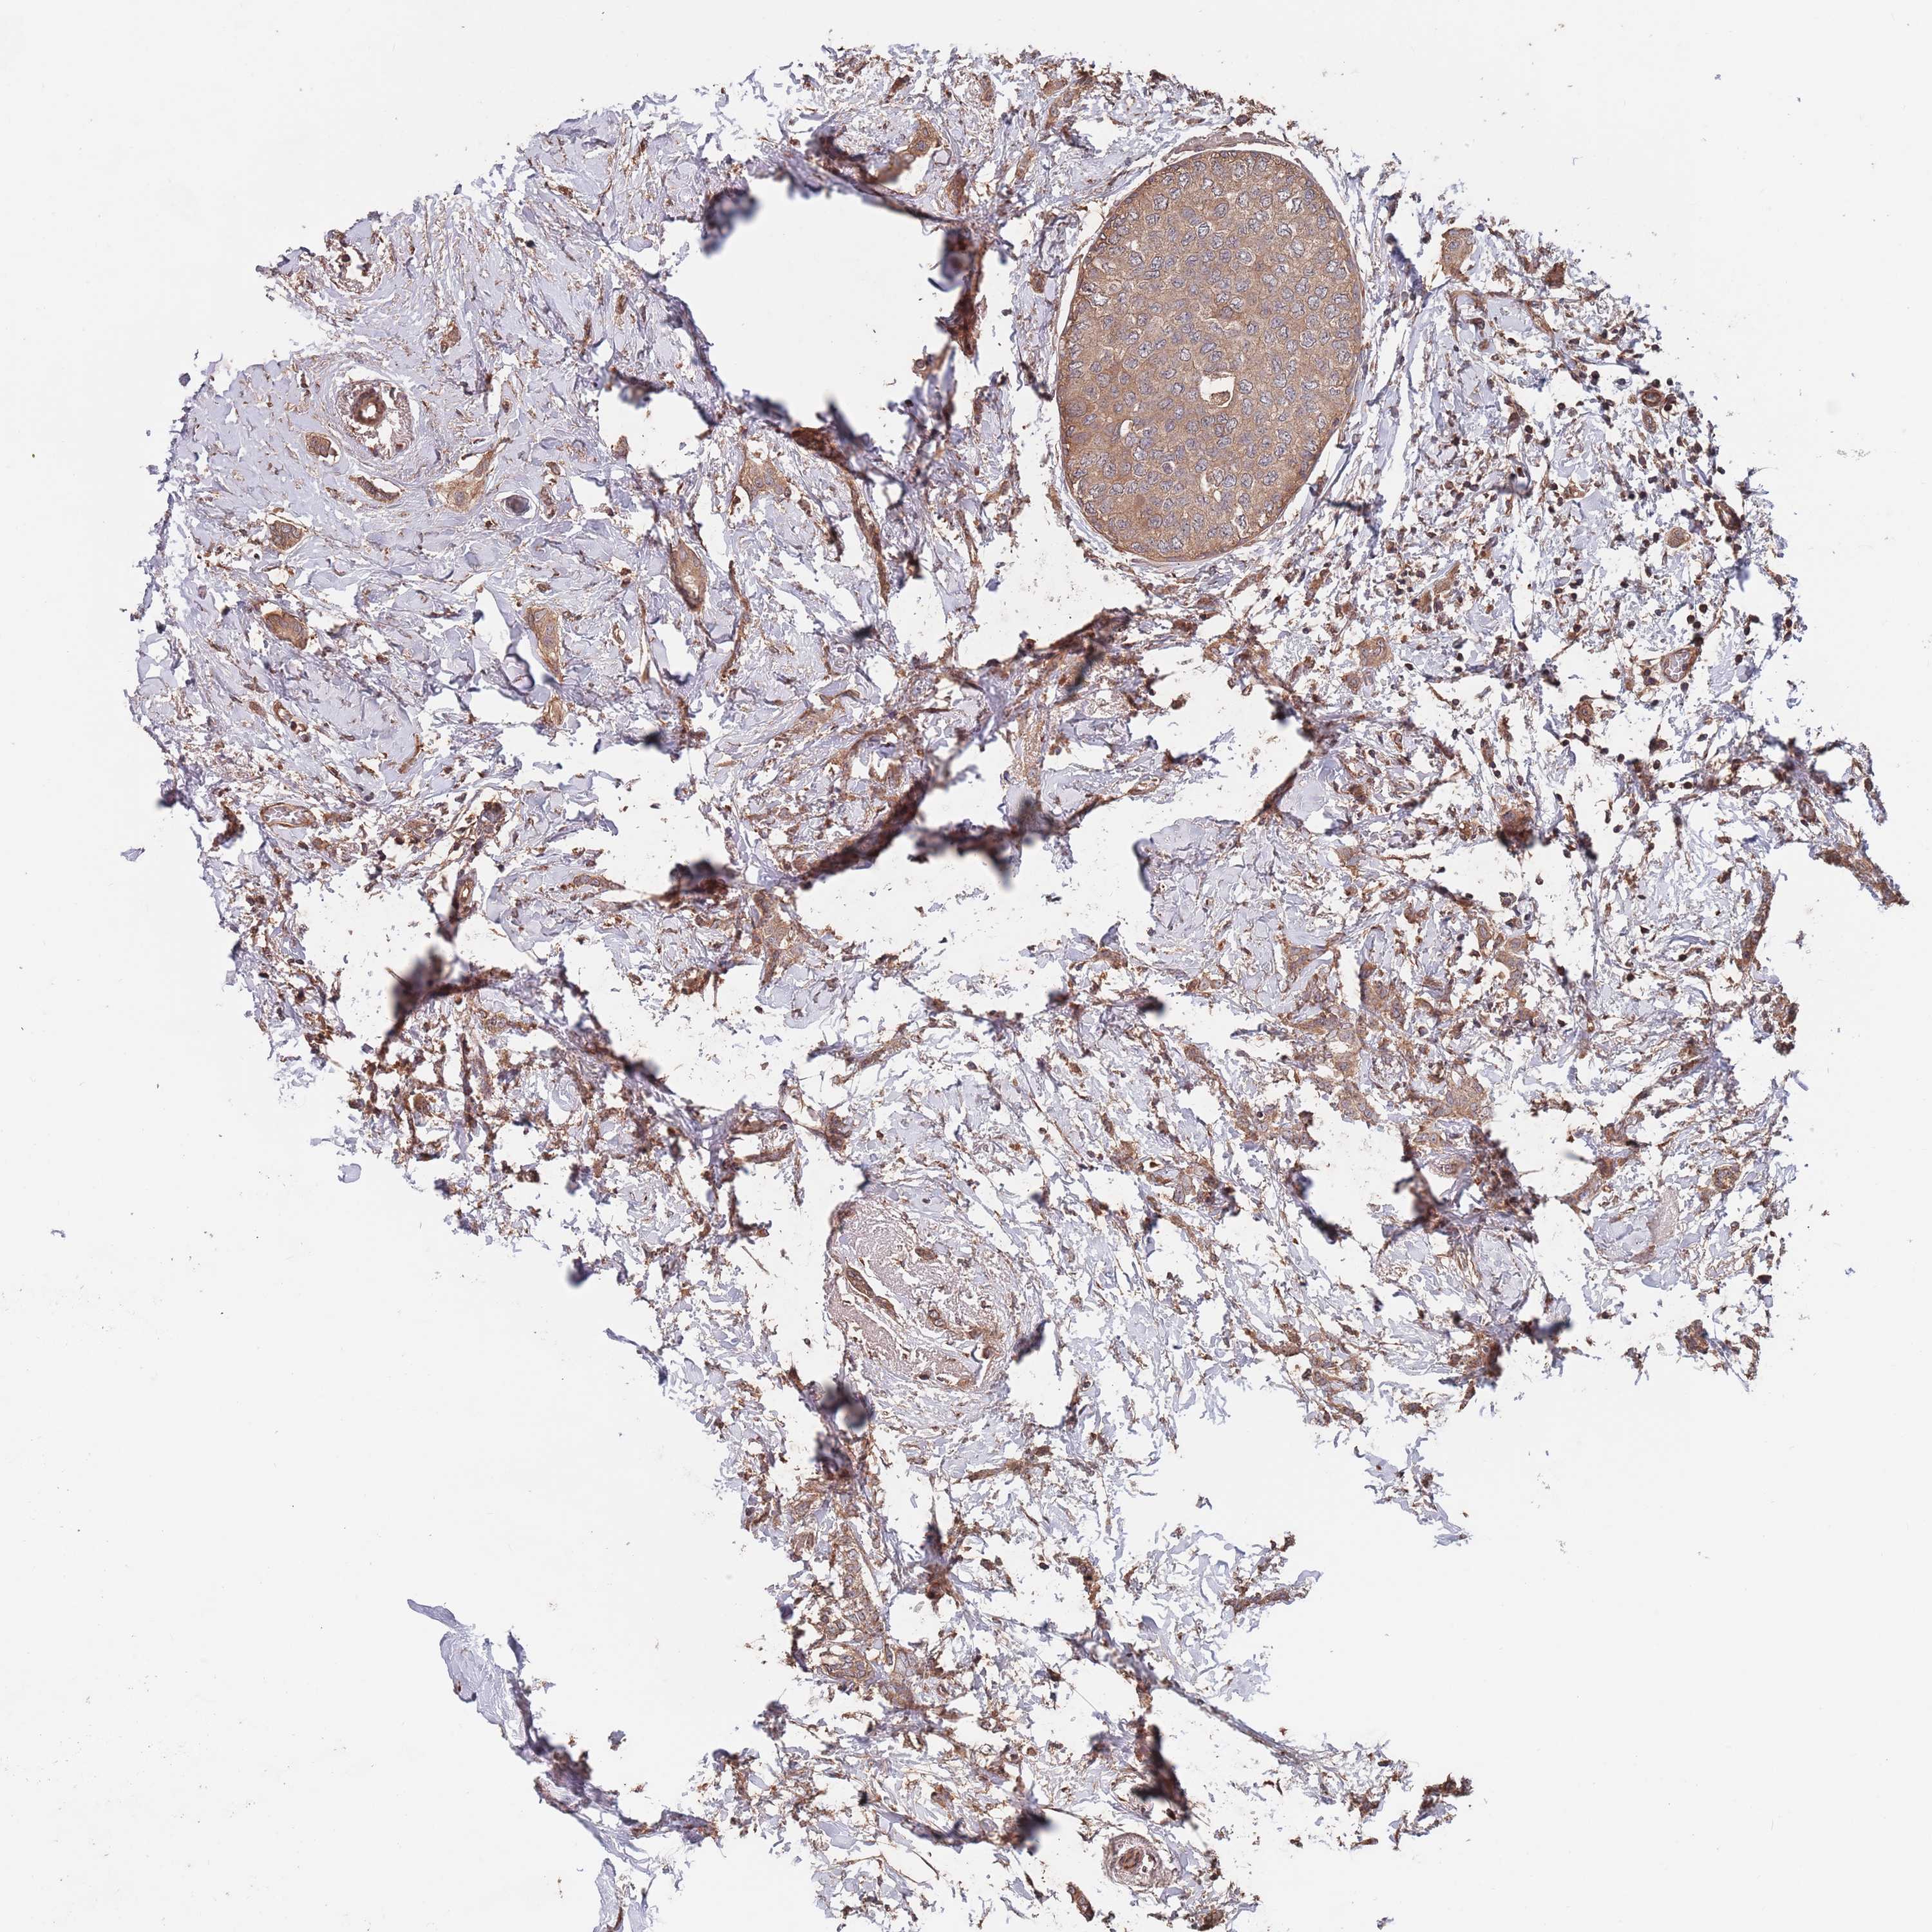

BRCA TCGA BRCA VALIDATION PROTEIN EXPRESSION